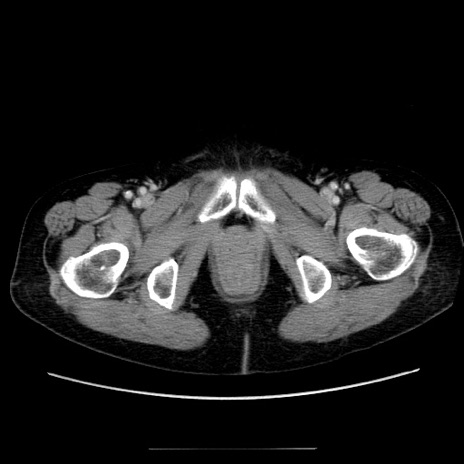

【症例】70歳代女性

【主訴】お腹が張る

【現病歴】1週間くらい前から腹部膨満の自覚あり。昨日夜から増悪したため、本日救急外来受診。

【身体所見】意識清明、BT 36.5℃、BP 165/106mmHg、HR 80bpm、SpO2 98%、腹部:膨満、軟、自発痛・圧痛なし、触診にて不快感あり、腸蠕動音:減弱

【データ】WBC 12600、CRP 1.04